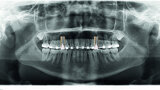

Orthodontic management of maxillary lateral incisors agenesis